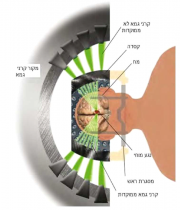

| 05:21, 5 באוגוסט 2014 | רדיו-כירורגיה.png (קובץ) |  |

268 קילו־בייטים | Motyk | 1 | |